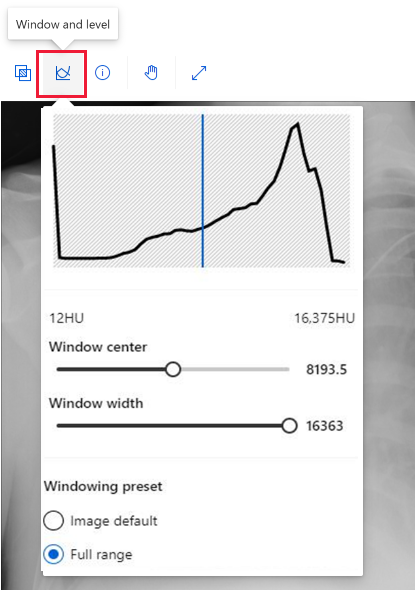

虽然你在标记医学图像时使用的工具与其他图像相同,你也可以使用另一个工具来处理 DICOM 图像,如以下屏幕截图所示:

选择“窗口和级别”工具,以更改图像的强度。 此工具只可用于 DICOM 图像。